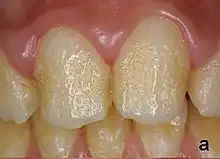

Pitting enamel hypoplasia, in an individual with amelogenesis imperfecta.

Enamel hypoplasia can take a variety of forms, but all types are associated with a reduction of enamel formation due to disruption in ameloblast production.[1] One of the most common types, Pitting Enamel Hypoplasia (PEH), ranges from small circular pinpricks to larger irregular depressions.[2] Pits also vary in how they occur on a tooth surface, some forming rows and others more randomly scattered.[3] PEH can be associated with other types of hypoplasia, but it is often the only defect observed.[4] Causes of PEH can range from genetic conditions to environmental factors, and the frequency of occurrence varies substantially between populations and species, likely due to environmental, genetic and health differences. The most striking example of this is in Paranthropus robustus, with half of all primary molars, and a quarter of permanent molars, displaying PEH defects, thought to be caused by a specific genetic condition, amelogenesis imperfecta.[1]